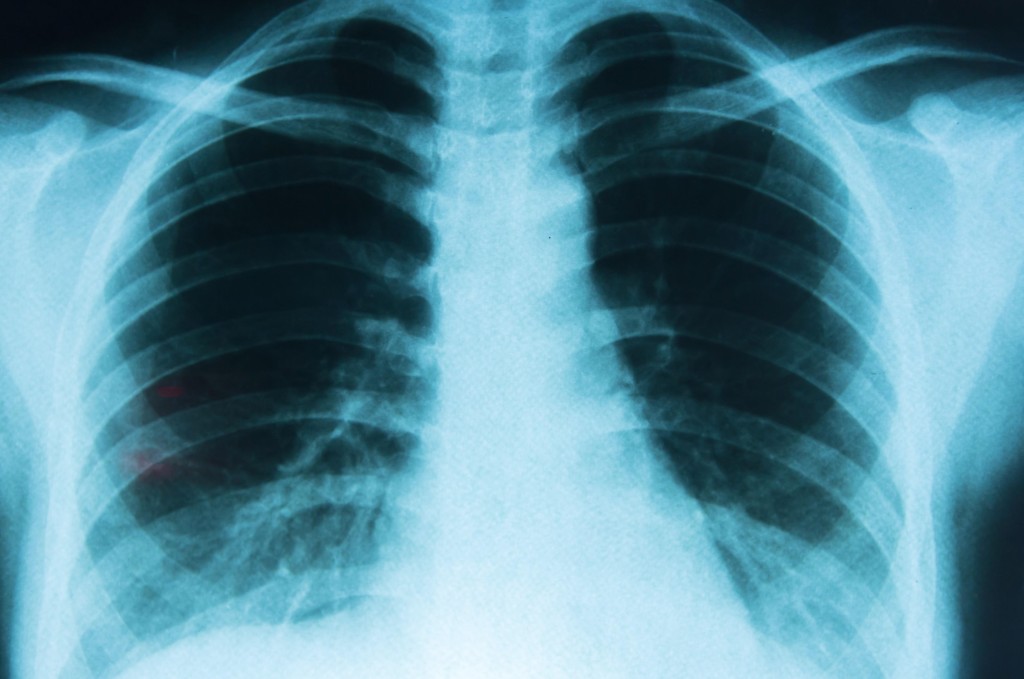

圖片來源:MedlinePlus